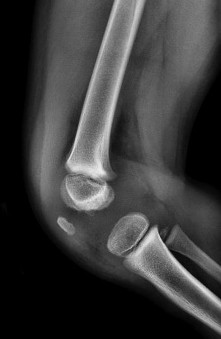

A 5-year-old boy presents with an extension-type Gartland III supracondylar humerus fracture after a fall.

On examination, his hand is well-perfused (pink) with brisk capillary refill, but the radial pulse is absent. What is the most appropriate initial management?